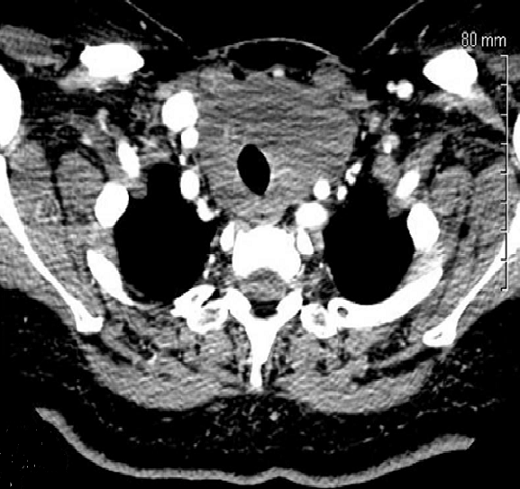

La thyroïdite de Riedel représente la forme la plus rare de thyroïdite chronique. Elle est caractérisée par l'apparition d'une fibrose infiltrative et extensive entraînant une destruction de la thyroïde et s'étendant aux organes de voisinage. Son étiopathogénie demeure inconnue. Son diagnostic est anatomopathologique. Sa prise en charge reste discutée. Patiente âgée de 47 ans, diabétique a consulté pour une tuméfaction basi-cervicale antérieure évoluant depuis 2 mois, rapidement évolutive, associée à une dysphagie et une dyspnée d'effort, sans dysphonie ni signes de dysthyroïdie. L'examen physique a révélé une formation basi-cervicale dure, mal limitée, indolore, mobile à la déglutition, de 10 cm de grand axe. Les aires ganglionnaires étaient libres. Le bilan thyroïdien était normal. L'échographie cervicale a retrouvé une thyroïde augmentée de taille, hétérogène sans nodules décelables. La TDM cervicale a objectivé une hypertrophie hypodense de la thyroïde, sans extension intra-thoracique. Cette hypertrophie englobait les axes carotidiens primitifs droits et gauches. Plusieurs diagnostics ont été évoqués particulièrement le cancer thyroïdien invasif (carcinome anaplasique), la forme fibreuse de la thyroïdite d'Hashimoto et le lymphome thyroïdien. En per-opératoire, la glande thyroïde était dure, fibrosée, inextirpable et englobait la trachée et les axes vasculaires du cou des 2 côtés. Une biopsie en quartier d'orange a été alors réalisée. L'examen anatomopathologique a conclut à une thyroïdite de Riedel. La patiente a été adressée en endocrinologie où elle a été mise sous corticoïdes L'évolution était favorable avec diminution de la taille du goitre et disparition des signes de compression.